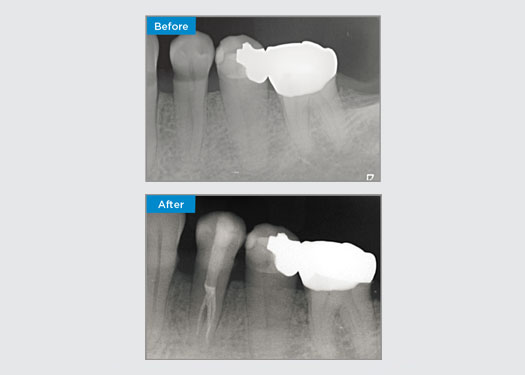

El paciente presentó pulpitis irreversible en la pieza dental 46. A partir de la radiografía preoperatoria, la pieza dental 46 se presenta con una raíz distal adicional (morfología dental Radix Entromolaris). Una escaneo CBCT ha confirmado la presencia de raíz distolingual con curvatura grave de la raíz. Una cuidadosa selección de limas es fundamental para esta raíz distobucal delicada.

Dr. Jack Lin, endodoncista, Sídney, NSW Australia